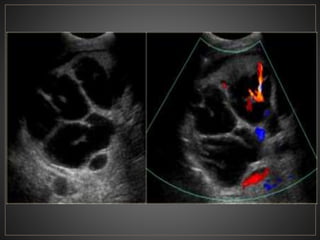

CPRE: Dilataciones saculares de CBIH. TC: Simple:Áreas redondas, hipointensas en topografía de CBIH. Contraste: Signo del punteado central. RM: T2: Espacios quísticos hiperdensos

• #52 USG en escala de grises donde se observa una dilatación de los conductos biliares intrahepaticos, con el signo del punteado central, a la aplicacion de doppler color se percibe flujo en las venas portales.

• #53 El CT axial con contraste muestra una dilatación masiva de los conductos biliares intrahepáticos. punto "central" o "excéntrico" en muchas de las estructuras quísticas, que representan las venas portas, un clásico hallazgo de imágenes en la enfermedad de Caroli.